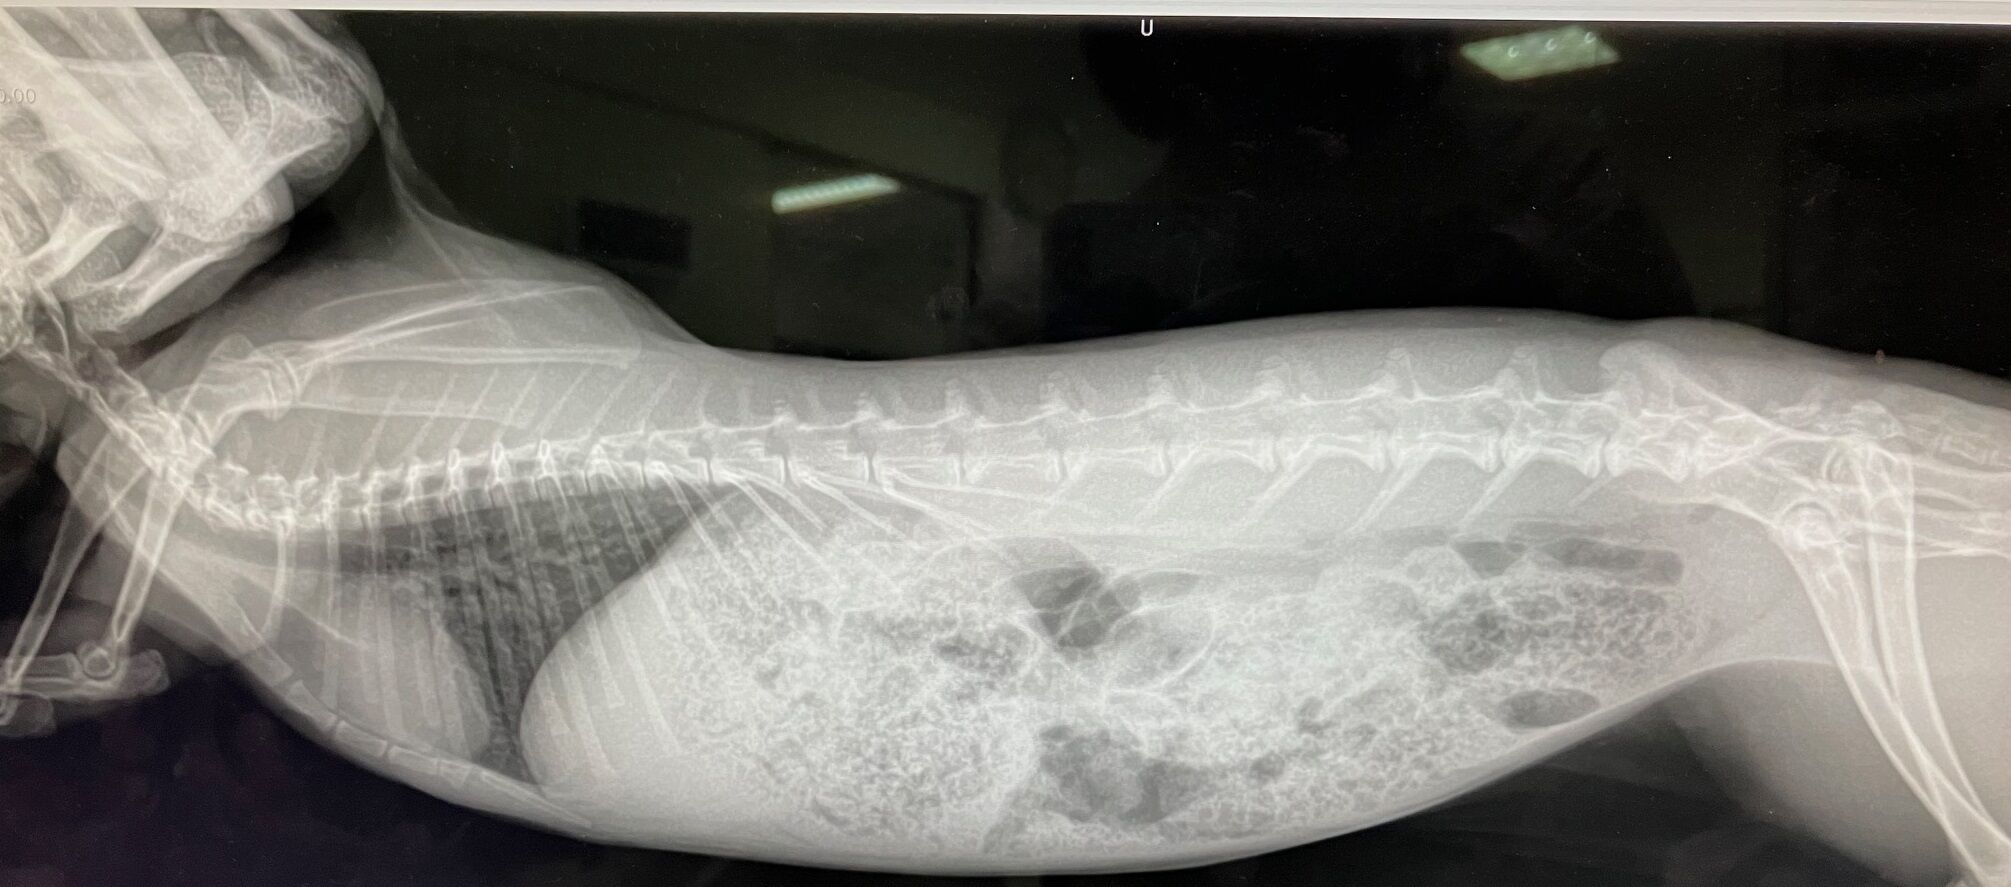

触診で閉塞=胃拡張などなさそでしたが念のためレントゲンもお願いしました。

盲腸うったい、盲腸便秘気味、ガスもそこそこだということで、

ステロイド点滴、と飲み薬いただく。